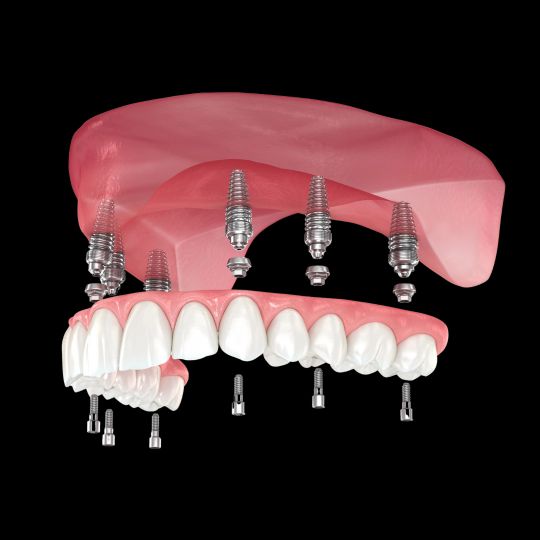

«Мы — одна из немногих стоматологических клиник Молдовы, которая не только обещает, но и действительно выполняет установку имплантов и фиксирует временные зубы уже в день операции или на следующий день. Это стало возможным благодаря современным технологиям, которыми оснащена клиника Punto Bianco (цифровые оттиски, выполненные с помощью самого современного интраорального сканера, 3D-томография прямо в клинике, собственная цифровая лаборатория), а также мультидисциплинарной команде с большим опытом в полном и сложном восстановлении зубных рядов.»